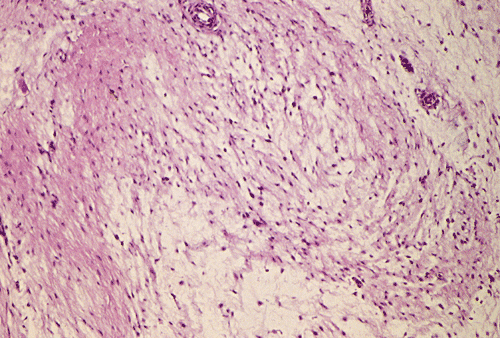

Panel A, B, and C are taken from the one area. Panel D, E, F, and G are taken from another area. Panel H and I are taken from areas with similar histologic features but distinctly separately on the same slide.

On low-magnifaction (Panel A and D), the lesional tissue appears to have generalized myomatous changes. No entrapped skeletal muscle fibers are found. The tumor cells tended to group into areas with variable cellularity that range from low- to, at most, moderate-cellularity. The hypocellular areas (Panel  B and C) contain sparsely spaced bland spindle cells in a bluish myxomatous background. The nuclei are elongated and mostly normochromatic. A few hyperchromatic nuclei are present and they are compatible with degenerative atypia (ancient change).

Islands with increased cellularity are present in some areas (Panel D, E, F, and G). These islands comprise about 30-40% of the lesional tissue. The cytologic features of the tumor cells in these areas are almost identical to that of the hypocellular areas except that the cellularity was increased. No mitotic figures are found in these areas. Focal hypervascularity are often found in areas with hypercellularity. No cellular condensation around blood vessels are noted (Panel  H and I).